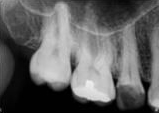

antes depois